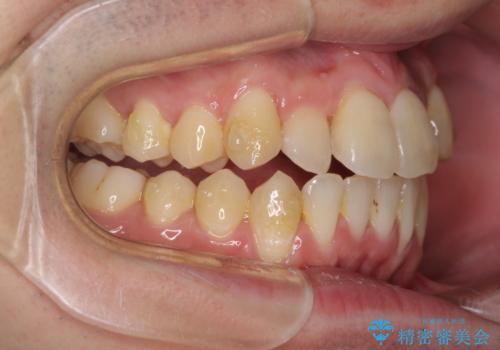

前歯のクロスバイト インビザラインによる矯正治療

- 上下のクロスバイトと前歯のデコボコを気にして来院された患者様です。

インビザラインを用い、IPR(歯と歯の間を削る)と歯列全体を拡大させることで、歯並びを整えていくこととしました。

上下ともに歯列全体を後方に移動させるため、上下の親知らずを抜歯することとしました。

奥に位置していた上の前歯が下の前歯を乗り越える際、奥歯でものを咬むことができず、辛い時期が続きました。